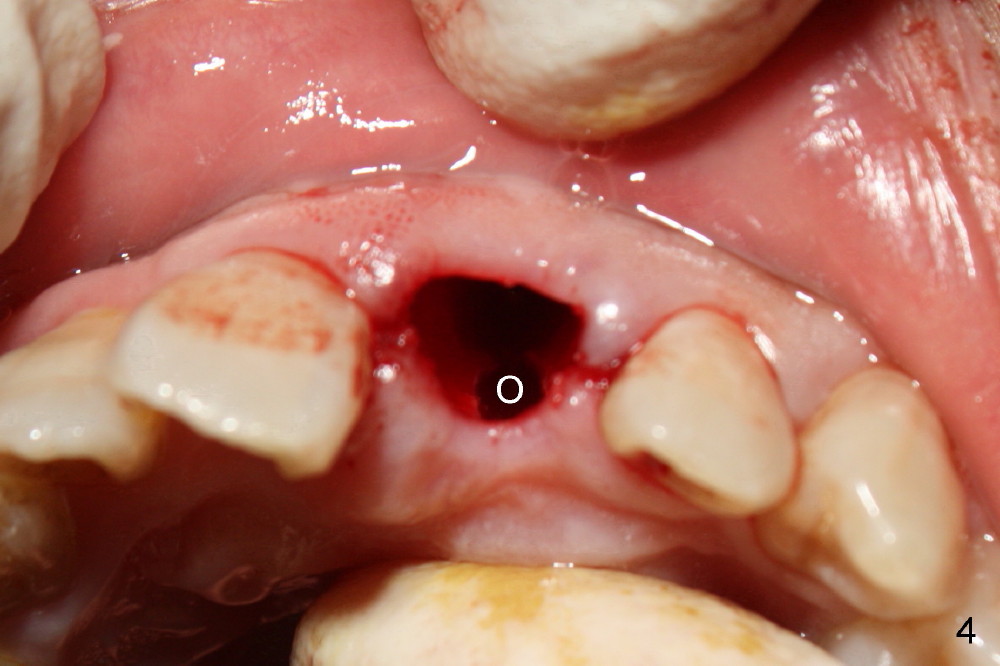

The upper right central incisor (Fig.1: #9) fractures subgingivally due to trauma for a 40-year-old man. The incisive canal is large (I) and close to the root of the central incisor. After extraction, the osteotomy (Fig.3b, 4: O) is made with 2 mm pilot drill (Fig.2: D) on the lingual wall (Fig.3a: L) of the socket (Fig.3a: S). To push the incisive canal mesially, the osteotomy is enlarged by 3.5x21 mm and 4x21 mm tapered osteotomes (Fig.5,6: O). Due to the lingual slope (Fig.7a arrow), the osteotome (blue outline) starts to deviate bucally. To reduce this tendency, the coronal portion of the lingual slope is removed (Fig.7b: yellow circle). The final implant (4.5x20 mm) is able to be placed as lingually as possible (Fig.7c, 8).

Bone expansion allows the implant (Fig.9 I) to have primary stability (insertion torque between 50 and 60 Ncm), since the cortex of the incisive canal is apparently intact. Allograft is placed in the labial gap (Fig.10, 11 *) following installation of the abutment (A). Finally an immediate provisional (Fig.10,12 P) is cemented. Fig.13,14 are taken 8 days postop. The patient returns 3 months postop (Fig.15,16). Osteointegration appears to have occurred (Fig.15 arrowheads) and is more obvious 9 months postop (Fig.17).